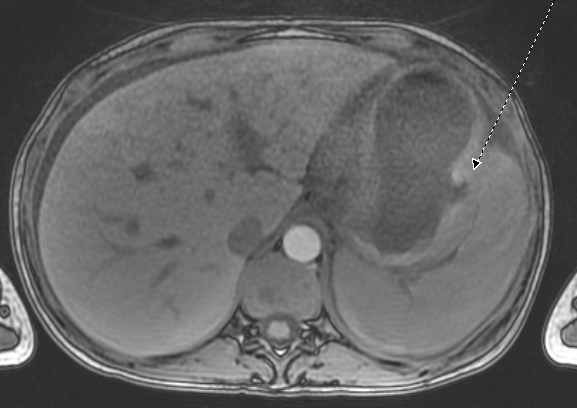

MRCP demonstrated wall thickening of the distal gastric body and gastric antrum concerning for tumor (Figure 1) with a right lower quadrant lesion suspected to be an enlarged right ovary (Figure 2). Innumerable sclerotic lesions were visualized in the axial and appendiceal skeleton suggestive of metastatic disease.  EGD was performed and showed gastric nodularity and friability. The ovarian mass was surgically excised. Figure 1: MRCP of abdomen with axial (left) and coronal views (right) of the stomach and ovarian masses, respectively.